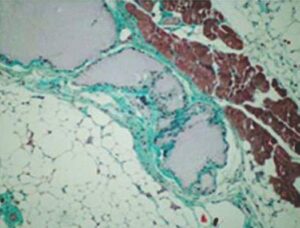

- totalement dégradable au bout de 2-3 ans tel que démontré par de nombreux tests (in vitro et in vivo) et par les études cliniques.

La dégradation d’un polymère dépend de sa structure et de sa nature. Ce gel est caractérisé par des diols, tout comme les polysaccharides naturels, ce qui veut dire qu’il est soumis au même processus biochimique que les polysaccharides naturels, comme l’acide hyaluronique.